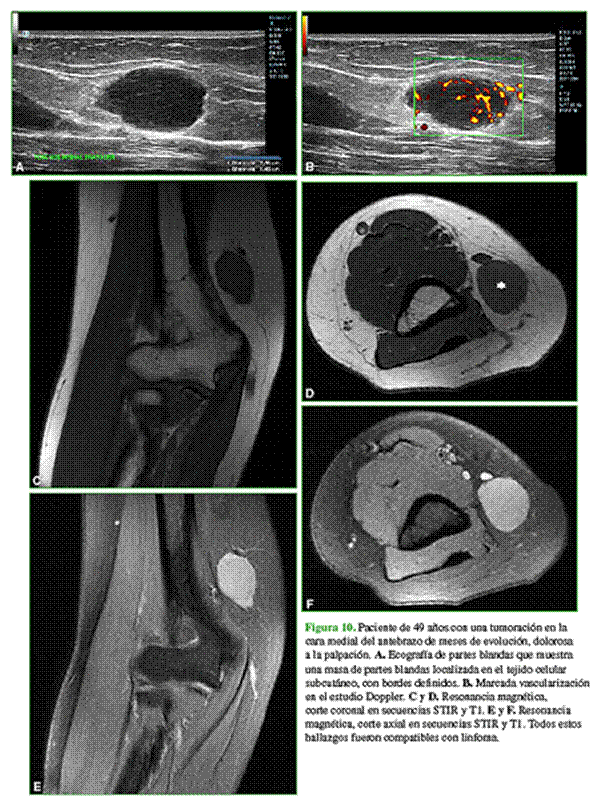

Los diagnósticos diferenciales más frecuentes son: otros sarcomas de partes blandas (fibrosarcoma o sarcoma sinovial), masas de partes blandas (miositis osificante) (Figura 8), schwannoma (Figura 9) y linfoma (Figura 10).